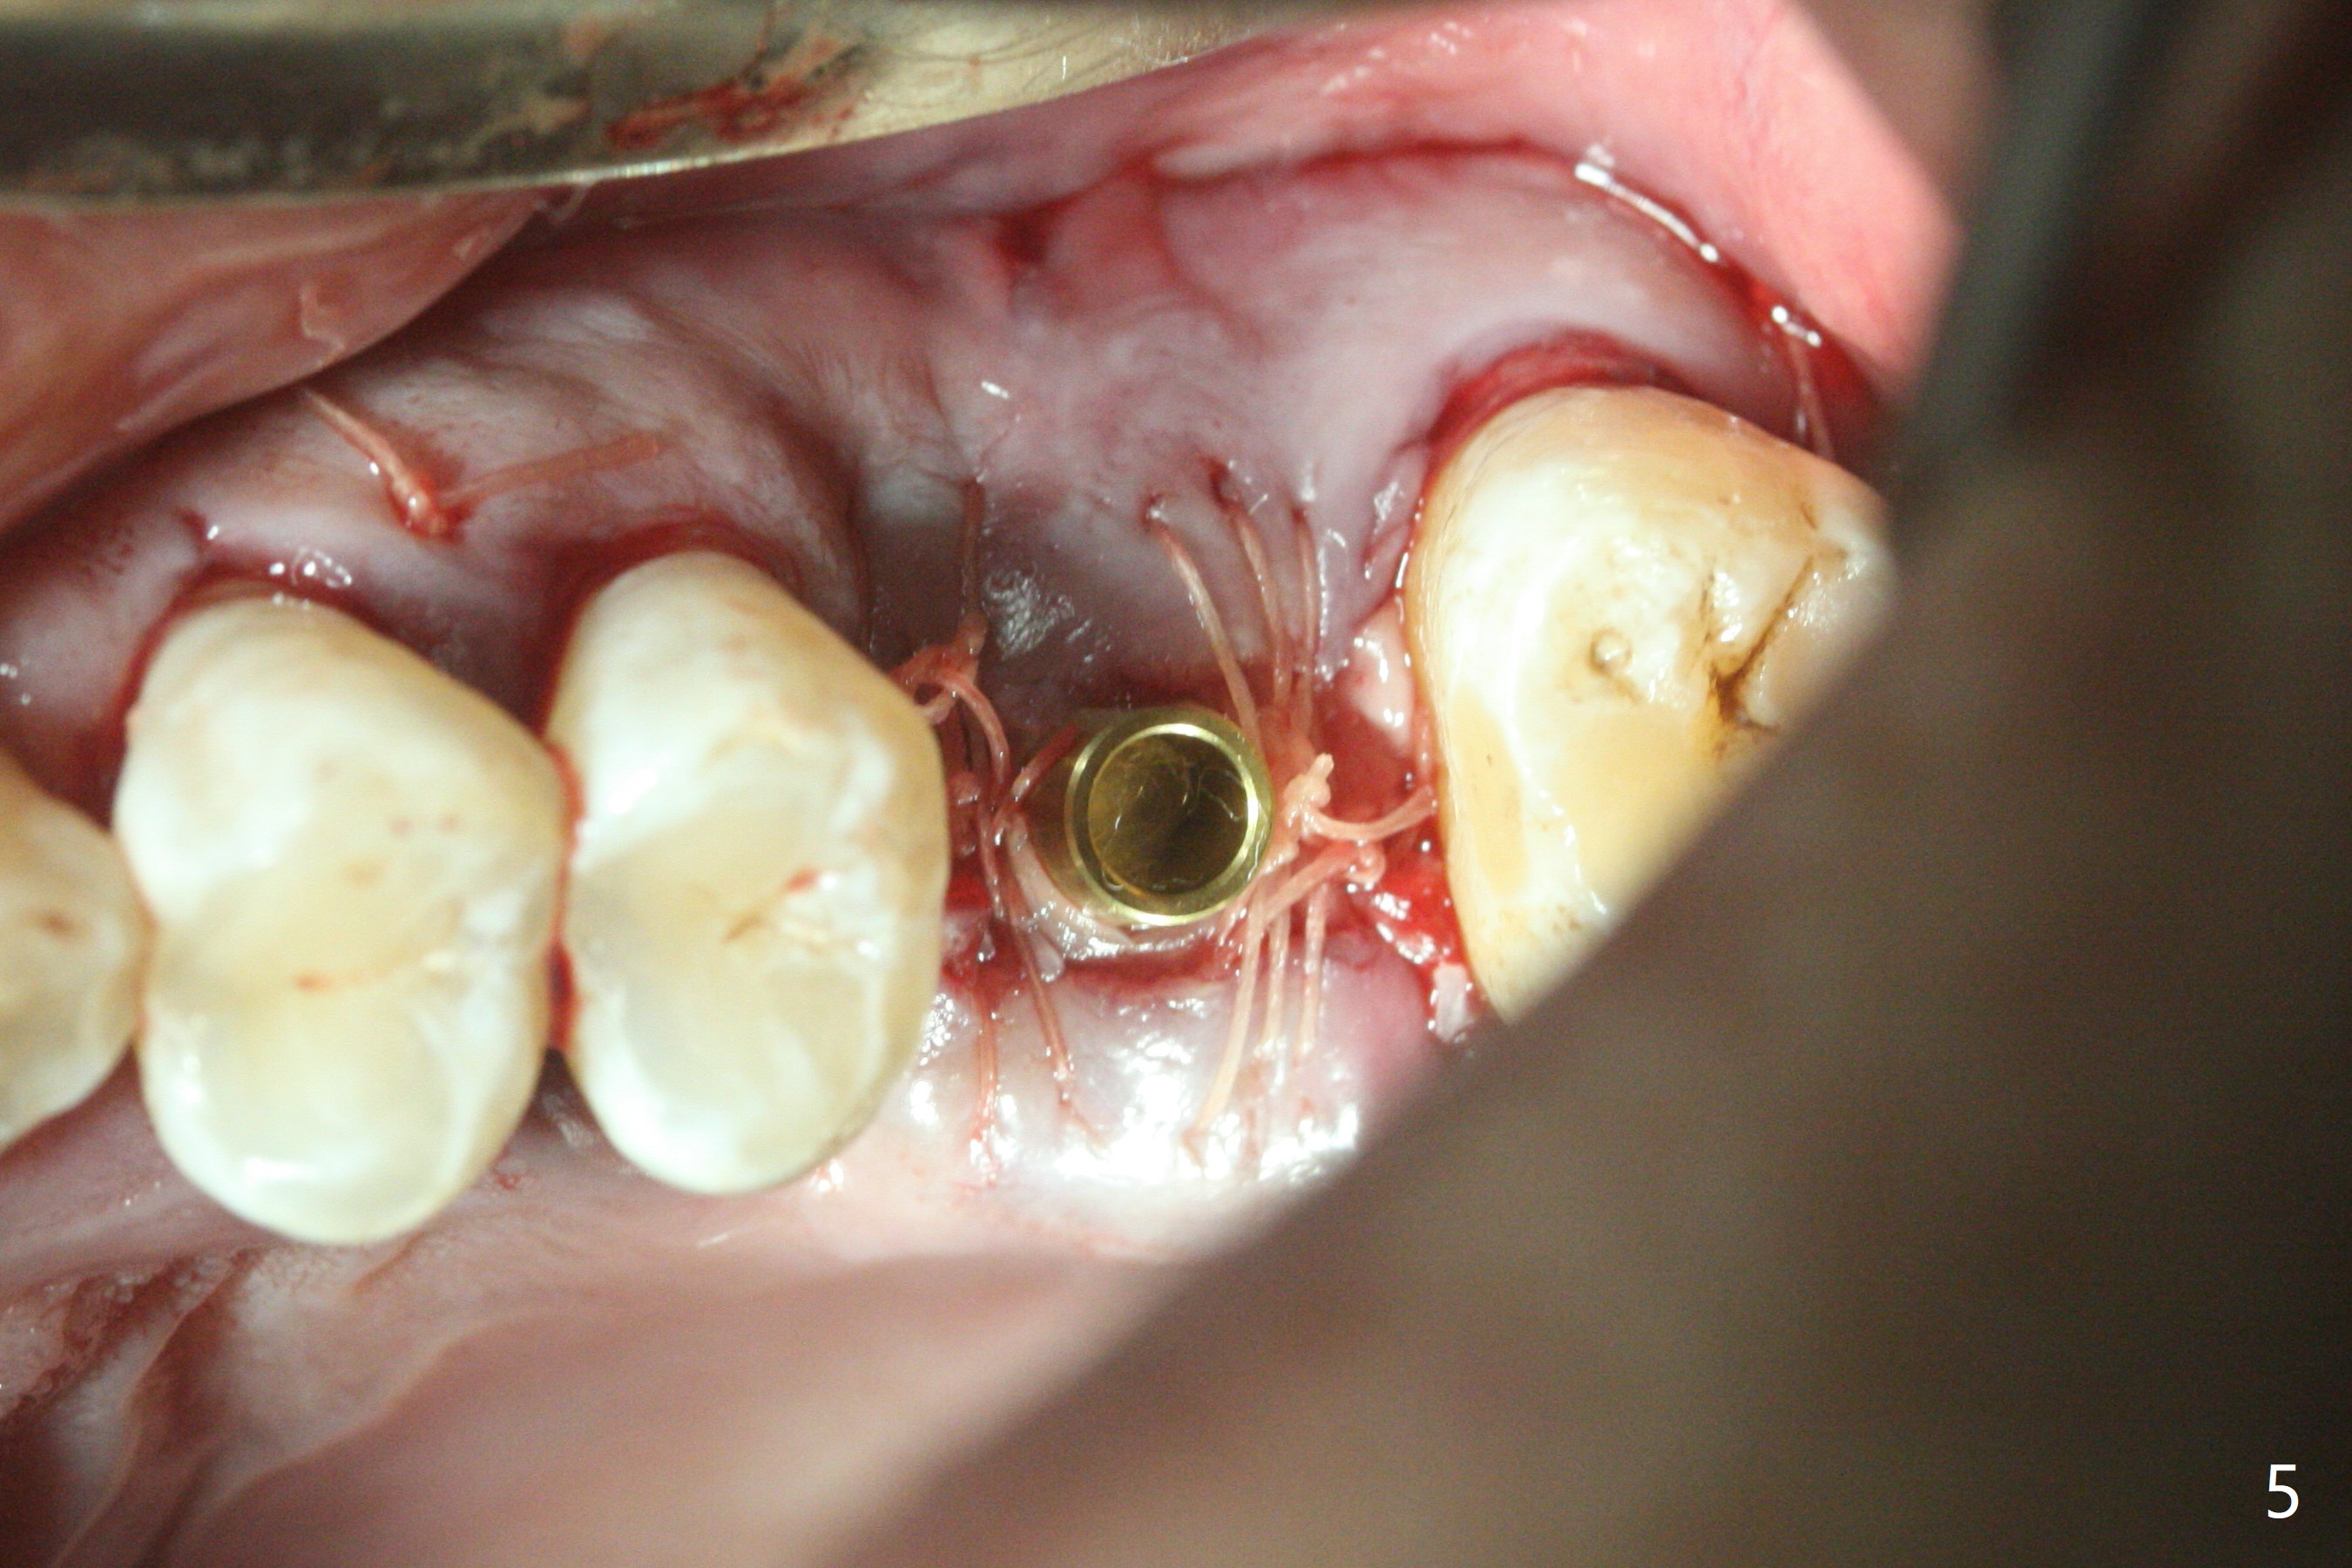

切开,使用导板完成初步钻洞,然后应用特殊上颌窦提升骨凿,顶端象环形刀,两侧有锥形刀刃(图一:箭头,防止骨凿突然进入上颌窦),由于窦底硬,骨凿并没有完全提升窦底(图二:红虚线)。使用短一号植体(图三),恰好进入上颌窦(没有骨粉),利用植体和基台固定骨粉(图四:*),覆盖两张PRF膜,将两侧厚的粘骨膜瓣尽量靠拢(图五)。最后树脂敷料。术后八天病人抱怨伤口和邻牙疼痛,骨粉被水牙线冲出来,进行邻牙咬合调整,疼痛即刻减轻(图六),再服用抗生素一周。一周后仍有轻度不适,局部牙龈正常,没有触痛。No Caries Magic Sinus Lifter 提升 Xin Wei, DDS, PhD, MS 1st edition 04/02/2021, last revision 04/18/2021